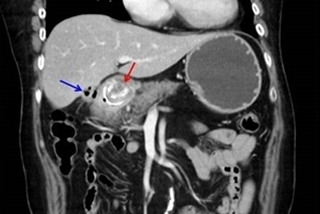

(優活健康網記者徐平/綜合報導)一位60多歲女子,長期有高血壓和糖尿病,也患有膽囊結石,平常斷斷續續有噁心嘔吐、上腹痛等膽囊結石典型症狀,近日因連續幾天上腹嚴重疼痛及頻繁嘔吐,甚至吐到全身無力才就醫。4公分膽囊掉出膽囊 胃完全阻塞胃鏡檢查顯示十二指腸處有一巨大結石,安排電腦斷層進一步檢查,發現有1顆約4公分的膽囊結石掉出膽囊,導致胃完全性阻塞,確診為膽囊結石的罕見併發症「布佛雷氏症候群(Bouveret's Syndrome)」,醫師安排手術取出十二指腸內的結石,個案術後復原良好,可正常進食,1週後康復返家。新竹馬偕紀念醫院一般外科葉孟青、張政傑醫師表示,由於個案長期患有膽囊結石,當結石脫落,並由膽腸間不正常的連通瘻管掉至小腸,嵌頓於十二指腸內,就造成胃部完全阻塞,醫學上稱為「布佛雷氏症候群(Bouveret's Syndrome)」,是膽囊結石的罕見併發之一。「布佛雷氏症候群」 僅1~3%發生率若沒有及時接受手術治療,可能產生膽囊炎、膽管炎、阻塞性黃疸、腸阻塞,甚至引起敗血症等併發症,膽囊結石病患中,僅1%患者臨床會呈現腸阻塞症狀,這是因為膽囊結石長期刺激造成慢性膽囊炎,時間一久結石磨穿發炎的膽囊壁,形成與小腸間的瘻管,結石因此掉入小腸造成阻塞。葉孟青醫師表示,阻塞處一般以小腸末端的迴腸最常見,因為迴腸是小腸最狹窄的地方,約佔60~70%,像個案阻塞在十二指腸處,造成胃出口阻塞的「布佛雷氏症候群」最罕見,僅1~3%左右。右上腹疼痛、餐後腹痛、嘔吐等症狀葉孟青醫師指出,國內每年有數萬人被診斷出有膽囊結石,多數患者沒有明顯症狀,很多都是健檢意外發現,不過約有20~30%的膽囊結石患者會伴隨如右上腹疼痛、餐後腹痛、嘔吐、噁心、右肩疼痛等症狀,一旦症狀頻繁或持續出現,例如劇痛、嘔吐超過6個小時,一定要立即就醫。